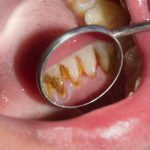

Plak yang mengalami kristalisasi menjadi karang gigi akan sangat sulit untuk dihilangkan dengan cara menggosok gigi. Perlu upaya lebih untuk menghancurkan karang gigi, salah satunya dengan berkunjung ke dokter gigi untuk melakukan scaling.

Padahal jika tidak dibersihkan, karang gigi bisa menyebabkan masalah kesehatan yang cukup serius loh. Inilah 4 dampak buruk karang gigi untuk kesehatan jika tidak dibersihkan.

Tempat Bakteri Berkembang Biak

Karang gigi bisa memberi efek yang serius pada kesehatan mulut, terutama bila muncul di atas garis gusi. Sebab, di sanalah tempat yang tepat bagi bakteri untuk bersarang, kemudian masuk ke dalam gusi dan merusaknya. Akibatnya, gusi akan mengalami iritasi dan peradangan.